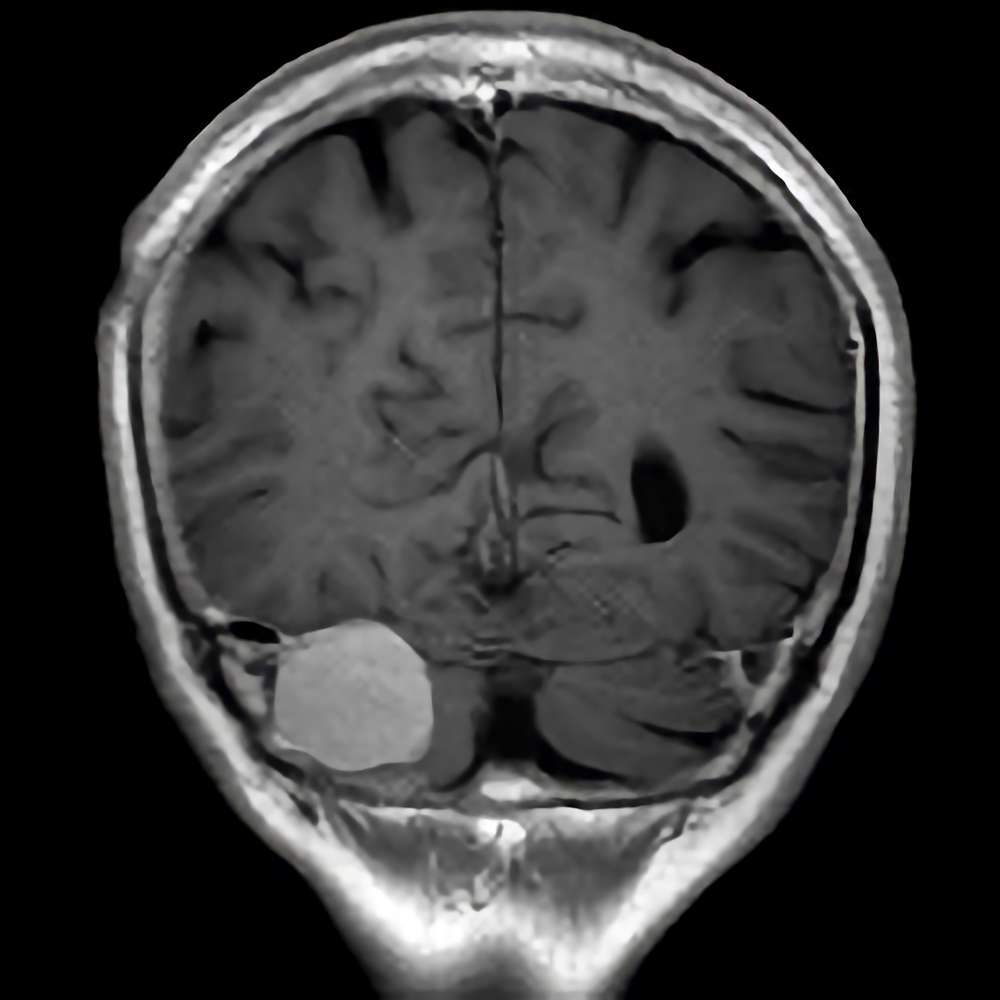

218

'21年9月

80代

左後頭頂葉腫瘤

頭蓋内腫瘍摘出術